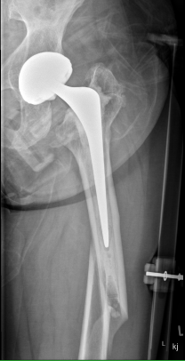

Type B2: Fracture around stem, femoral component loose

Management

A. Revision arthroplasty with long stem femoral implant +/- plate +/- cortical strut allograft

- distal fit (cemented / uncemented)

- must bypass distal extent of fracture by at least 2 cortical diameters

Fracture with stem subsidence around a polished tapered femoral stem treated with ORIF